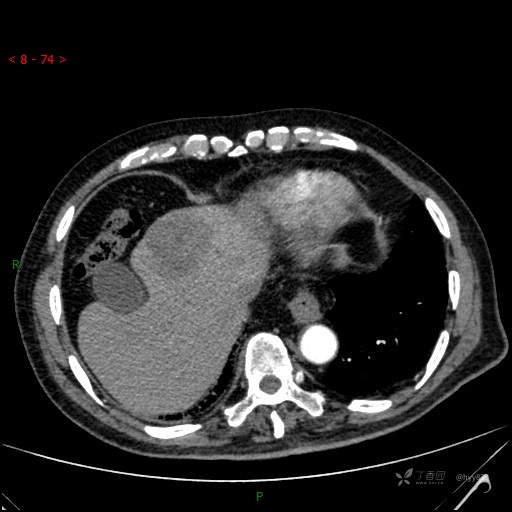

肝脏CT平扫

img

肝脓肿 (73)